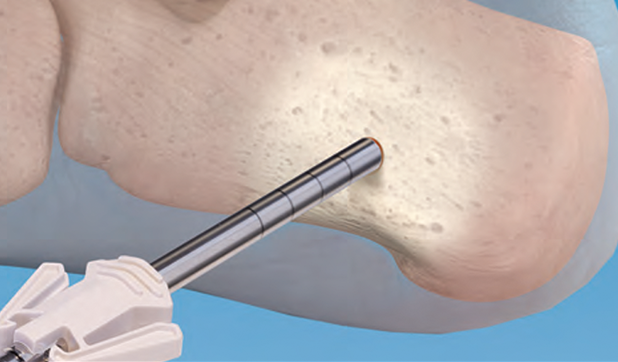

Dr. Gdalevitch - Minimally Invasive Percutaneous Approach for Hallux Valgus Deformities